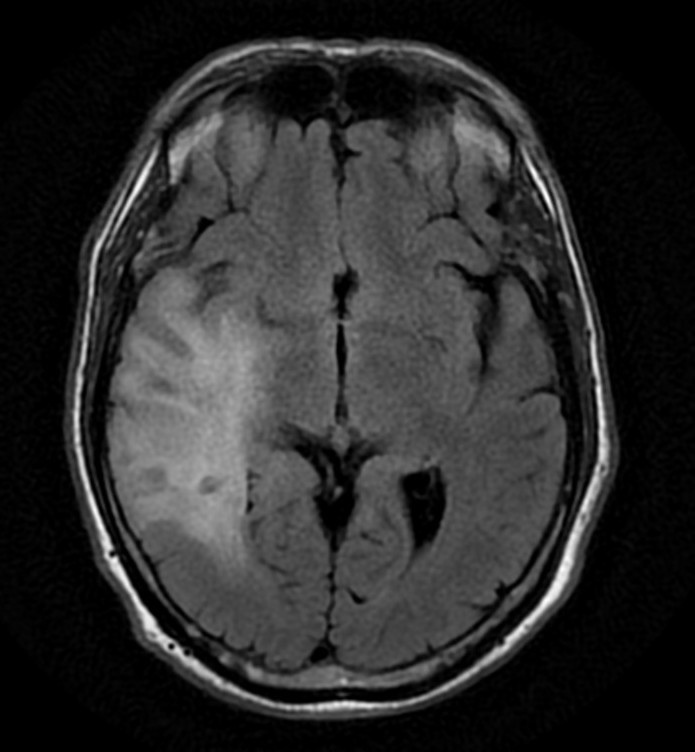

Santral Sinir Sisteminin Basit Anatomisi Sinir sistemi genel olarak santral sinir sistemi ve periferik sinir sistemi olarak ikiye ayrılır. Santral sinir sistemi beyin, beyin sapı, beyincik ve omurilikten oluşur. Periferik sinir sistemi ise omurilikten çıkan spinal sinirler ve otonom sinir sisteminden oluşur. MENİNKSLER (BEYİN ZARLARI) Beyin ve omurilik, kendisini darbelerden koruyan kranium ve omurga kanalı […]